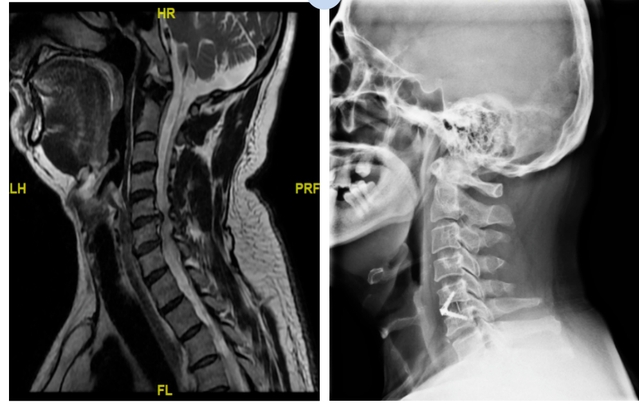

●一位患者被颈椎病困扰多年,颈椎长期不稳定且合并椎间盘突出,椎体后缘增生,韧带骨化,导致突出物的硬度很高,就像一块“石头”压迫脊髓,再不处理,将造成更加严重的后果。

颈椎手术毗邻关系复杂,伴有重要的神经血管等,从技术上需要医生具备精准的解剖结构专业知识和丰富的临床手术经验,手术难度大且风险系数高。探花直播 骨科主任言湛军组织协调骨科、麻醉科、医学影像科等科室,详细评估患者的情况,明确诊断并制定手术方案,最后决定为两位患者开展颈椎前路椎管减压、椎间融合内固定手术,通过微创治疗将突出物彻底切除。

术后患者椎间隙高度恢复,生理曲度恢复,神经受压解除;头部胀痛,右上肢放射痛得到缓解。

巨大的突出物已切除,椎间隙高度恢复,椎管容积扩大,神经压迫解除,双手麻木感消失。